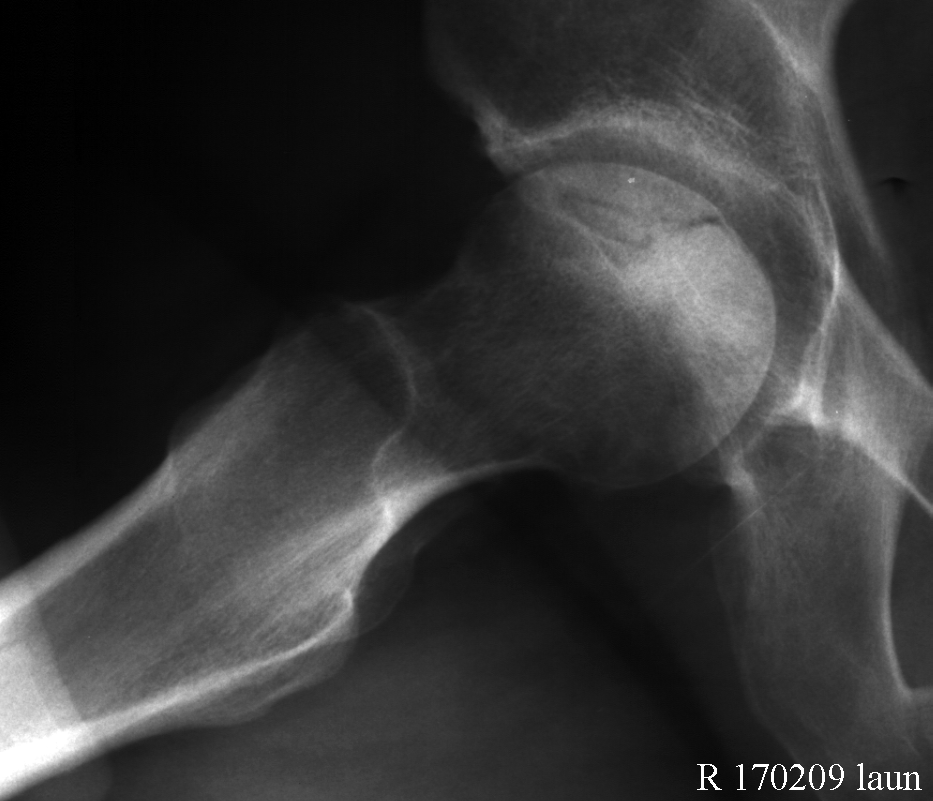

Диагностика ТБС рентгеном и асептический некроз: особенности лечения

Раздел: Снимки-откровения